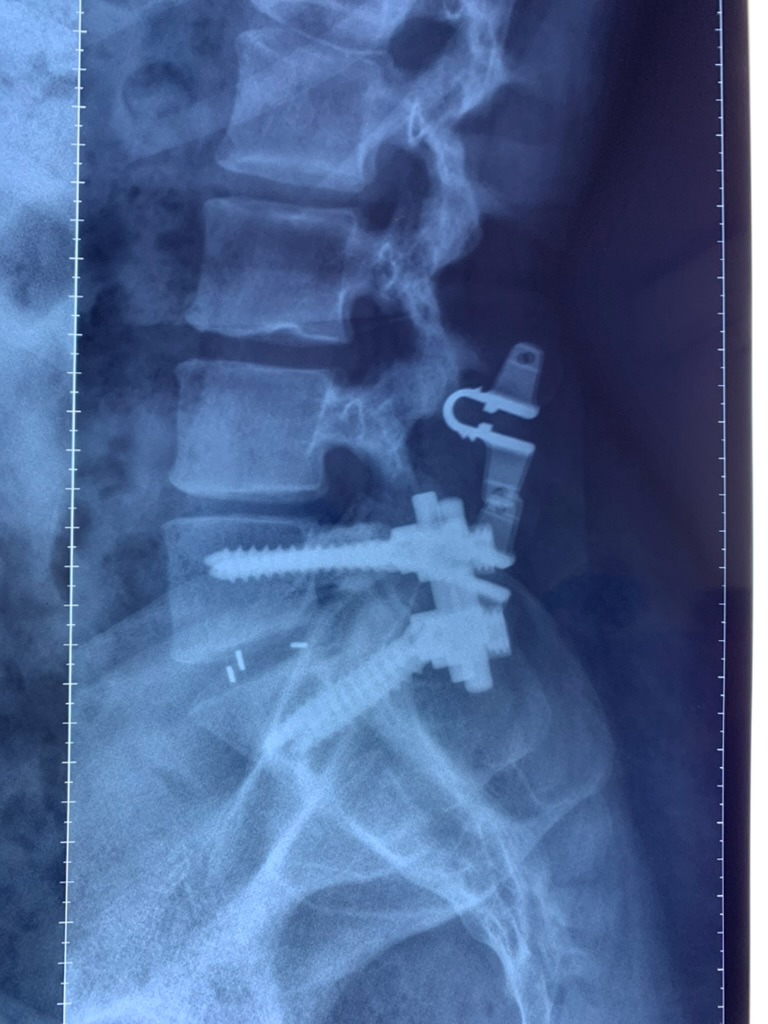

CIRUGIAS

RESULTADOS